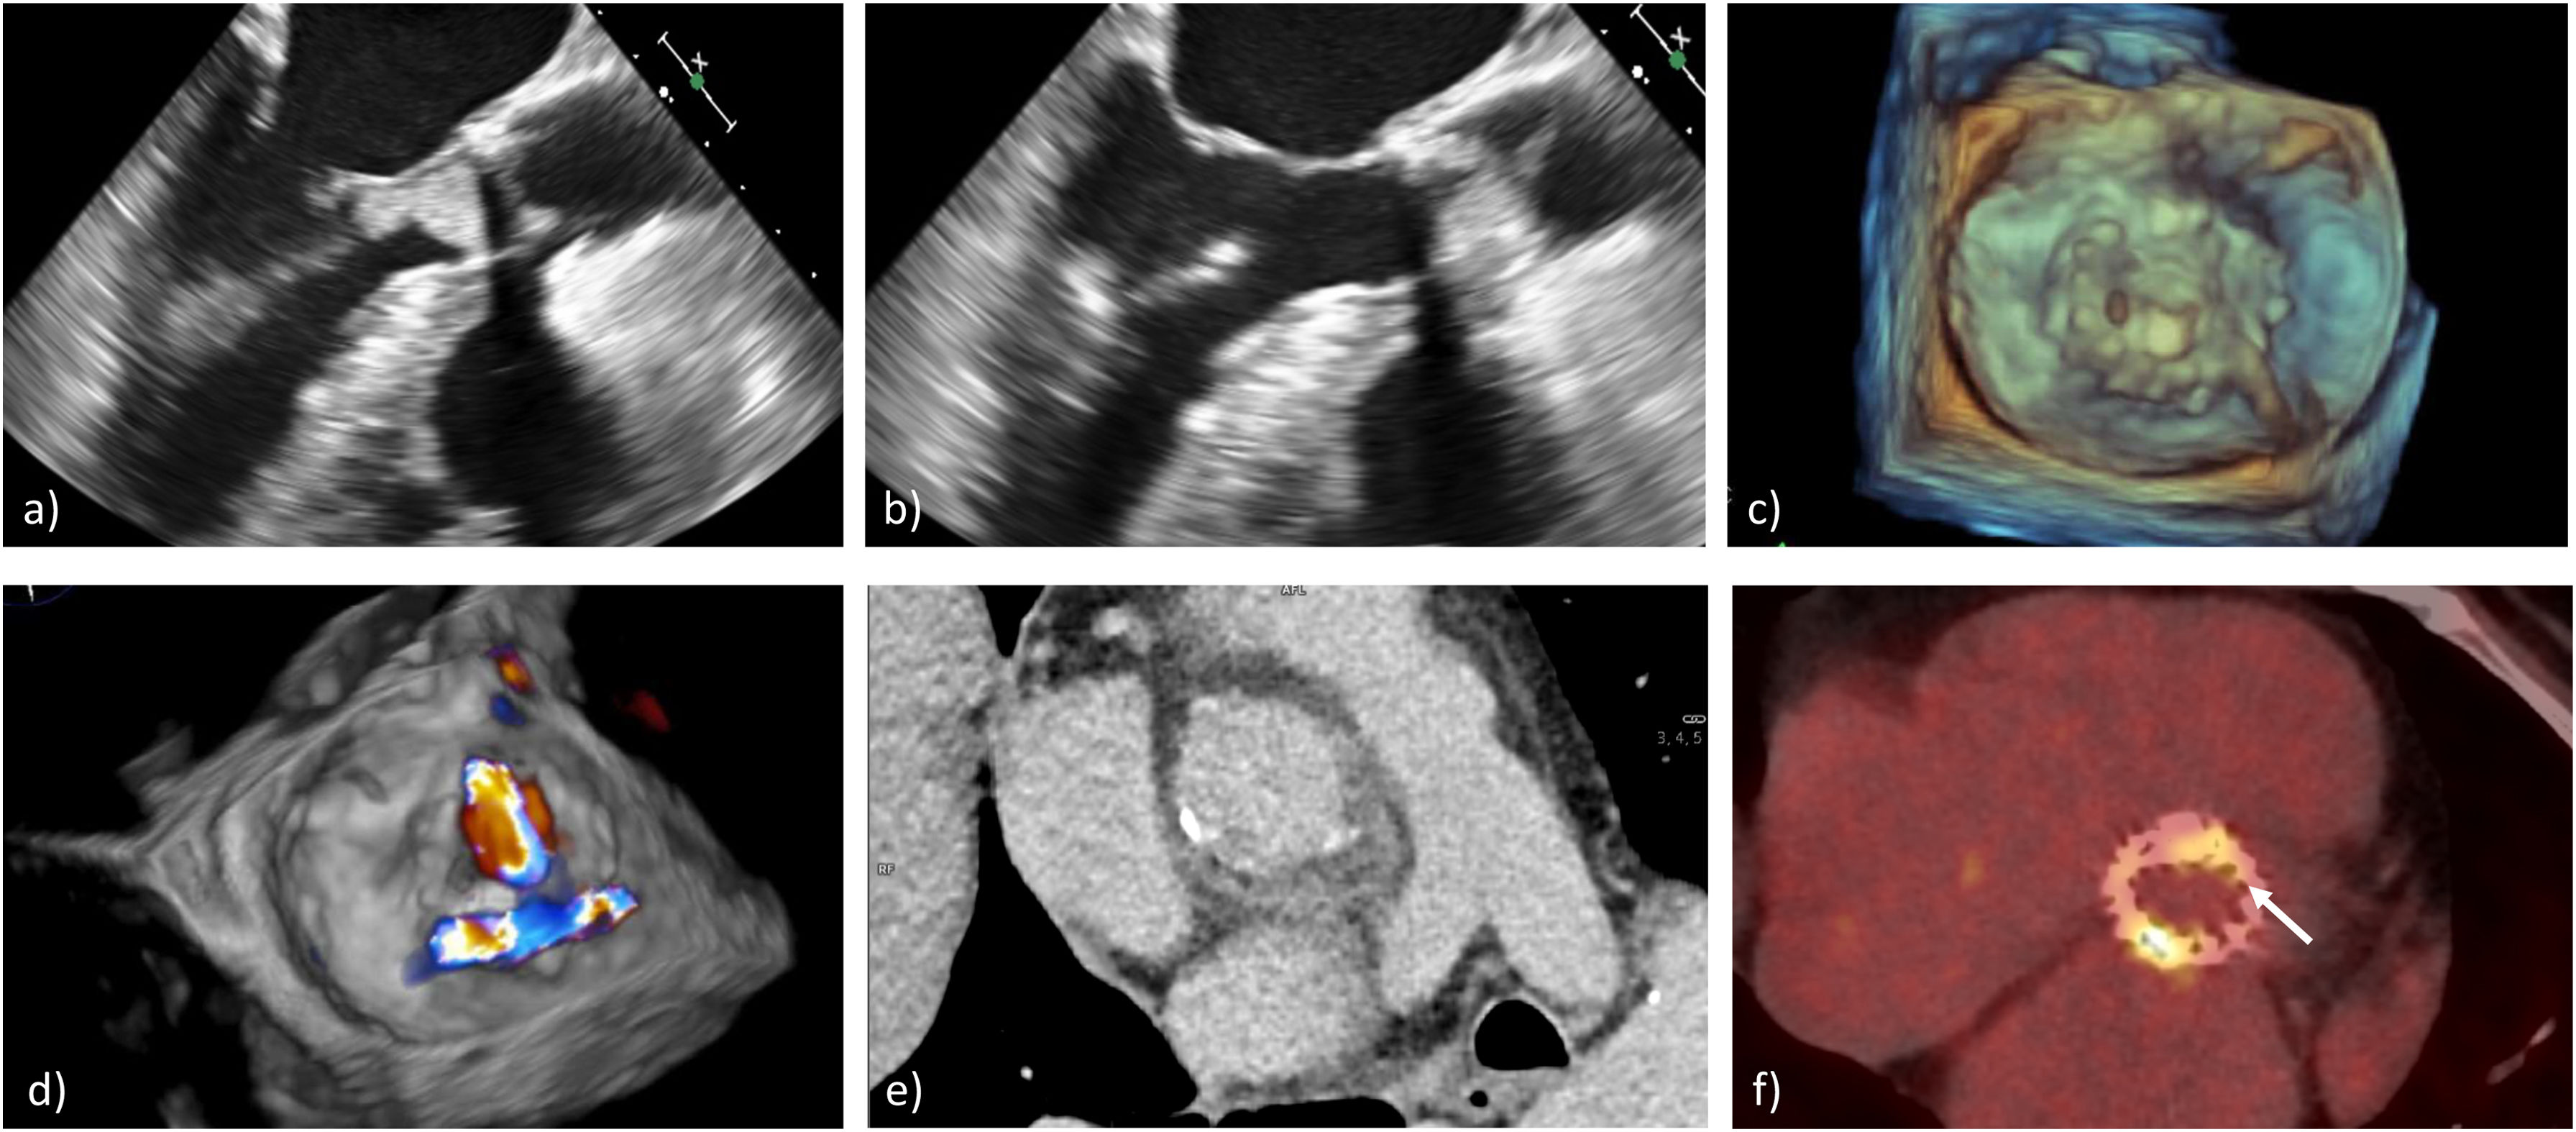

Los anillos, suturas y tejidos protésicos se endotelizan, lo cual actúa como protección, siendo el depósito de microtrombos plaquetarios el sustrato de adhesión para microorganismos durante episodios bacteriémicos. Los metales, como el titanio o el carbón pirolítico, no permiten, en ausencia de trombos, la adhesión de microorganismos. Por ello la infección, en las prótesis mecánicas, se produce en el anillo de sutura o en áreas de recirculación próximas, generando dehiscencias periprotésicas o extensión a tejidos adyacentes (fig. 1). En prótesis biológicas, la infección, al igual que en la EVN, tiende a iniciarse en las valvas50. Las infecciones de los dispositivos electrónicos intracardiacos no se asocian necesariamente a infecciones valvulares51.

Endocarditis protésica aórtica: a) dehiscencia periprotésica por EPV, b) prótesis mecánica aórtica infectada explantada, c) reconstrucción del anillo valvular con pericardio heterólogo, d) EPV mitral, e) prótesis mitral mecánica infectada explantada y f) integridad periprotésica mitral con vegetación en anillo de sutura.